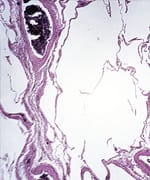

Breast carcinoma

Even after cells have undergone malignant transformation, there's a chance to reverse that process by forcing them to "differentiate" back into normal tissue-forming cells. Nutrients that promote the differentiation of breast cancer cells include: